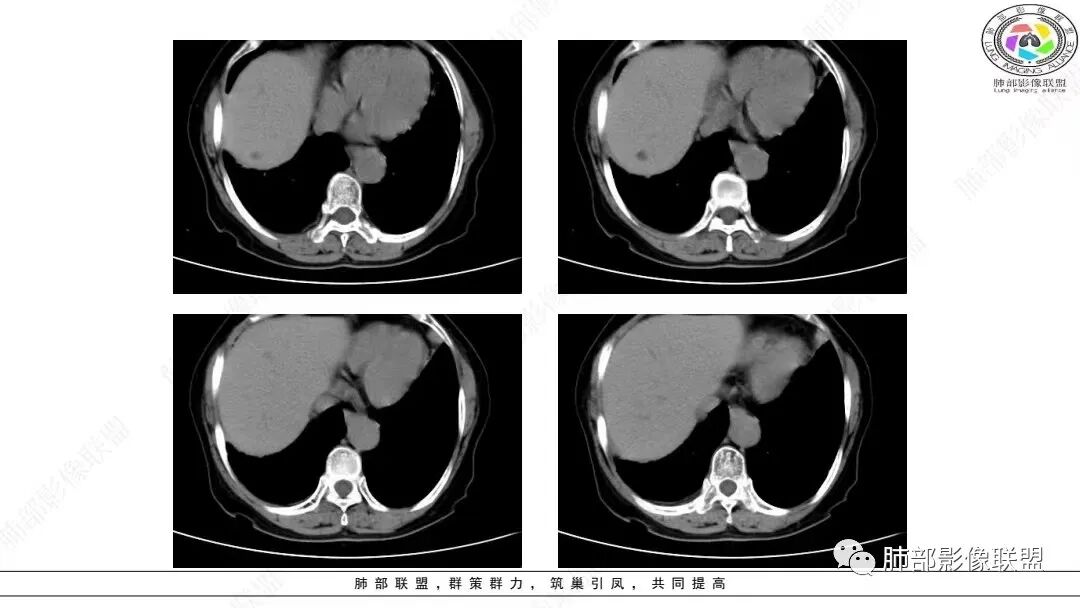

2.影像学特点:右肺上叶前段胸膜下不规则较大团块影,边界清楚欠光整,浅分叶,肺血管支气管出入,边缘膨隆胸膜凹陷具有一定张力,未见典型粗短毛刺,部分围以边界清楚的磨玻璃影,灶周小叶间隔增厚。块影密度不均,渐进性强化,可见砂砾样钙化,未见明显液化坏死或空洞。增强后病灶显示渐进性强化。MIP显示病灶内肺动脉穿行、并部分肺动脉受侵变细。纵隔及右锁骨上(胸廓入口)见肿大淋巴结。两肺可见多发大小不一的结节影,边界清楚,随机分布。

胸椎体溶骨性吸收破坏,突破骨皮质。腹部扫描未见肿块影。